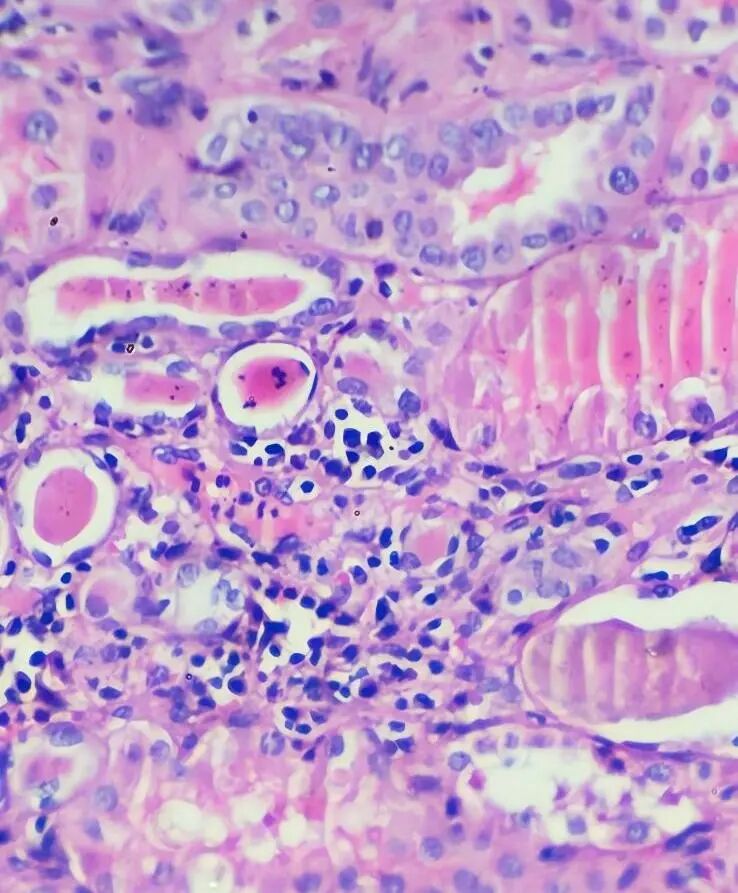

检查结果打破了侥幸:尿潜血2+、尿蛋白3+,24小时尿蛋白定量远超正常范围,进一步肾穿刺活检后,确诊为“肾型过敏性紫癜(局灶增生型紫癜型肾炎,ISKD分型IIIa型)”,还合并血小板减少。这个结果让她不解:“皮肤的问题,怎么会伤到肾?”

不少患者对肾穿刺存在顾虑,但它是诊断肾型过敏性紫癜的“金标准”。通过肾穿刺,医师能明确肾小球损伤的类型和程度(如ISKD分型)——像病例中的IIIa型,属于局灶增生性病变,这直接决定了治疗方案:是用基础药物控制,还是需要联合冲击治疗,避免“轻症过度治疗”或“重症治疗不足”。同时,肾穿刺还能与IgA肾病、狼疮性肾炎等相似疾病鉴别,避免误诊。